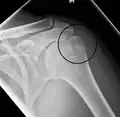

Proximal

Proximal humerus fractures most often occur among elderly people with osteoporosis who fall on an outstretched arm.[9] Less frequently, proximal fractures occur from motor vehicle accidents, gunshots, and violent muscle contractions from an electric shock or seizure.[10][5] Other risk factors for proximal fractures include having a low bone mineral density, having impaired vision and balance, and tobacco smoking.[11] A stress fracture of the proximal and shaft regions can occur after an excessive amount of throwing, such as pitching in baseball.[6]

Definitive diagnosis of humerus fractures is typically made through radiographic imaging. For proximal fractures, X-rays can be taken from a scapular anteroposterior (AP) view, which takes an image of the front of the shoulder region from an angle, a scapular Y view, which takes an image of the back of the shoulder region from an angle, and an axillar lateral view, which has the patient lie on his or her back, lift the bottom half of the arm up to the side, and have an image taken of the axilla region underneath the shoulder.[9] Fractures of the humerus shaft are usually correctly identified with radiographic images taken from the AP and lateral viewpoints.[12] Damage to the radial nerve from a shaft fracture can be identified by an inability to bend the hand backwards or by decreased sensation in the back of the hand.[5] Images of the distal region are often of poor quality due to the patient being unable to extend the elbow because of pain. If a severe distal fracture is suspected, then a computed tomography (CT) scan can provide greater detail of the fracture. Nondisplaced distal fractures may not be directly visible; they may only be visible due to fat being displaced because of internal bleeding in the elbow.[7]

Fractures of the humerus are classified based on the location of the fracture and then by the type of fracture. There are three locations that humerus fractures occur: at the proximal location, which is the top of the humerus near the shoulder, in the middle, which is at the shaft of the humerus, and the distal location, which is the bottom of the humerus near the elbow.[9] Proximal fractures are classified into one of four types of fractures based on the displacement of the greater tubercle, the lesser tubercle, the surgical neck, and the anatomical neck, which are the four parts of the proximal humerus, with fracture displacement being defined as at least one centimeter of separation or an angulation greater than 45 degrees. One-part fractures involve no displacement of any parts of the humerus, two-part fractures have one part displaced relative to the other three; three-part fractures have two displaced fragments, and four-part fractures have all fragments displaced from each other.[13][14][3] Fractures of the humerus shaft are subdivided into transverse fractures, spiral fractures, "butterfly" fractures, which are a combination of transverse and spiral fractures, and pathological fractures, which are fractures caused by medical conditions.[12] Distal fractures are split between supracondylar fractures, which are transverse fractures above the two condyles at the bottom of the humerus, and intercondylar fractures, which involve a T- or Y-shaped fracture that splits the condyles.[7]

One-part and two-part proximal fractures can be treated with a collar and cuff sling, adequate pain medicine, and follow up therapy. Two-part proximal fractures may require open or closed reduction depending on neurovascular injury, rotator cuff injury, dislocation, likelihood of union, and function. For three- and four-part proximal fractures, standard practice is to have open reduction and internal fixation to realign the separate parts of the proximal humerus. A humeral hemiarthroplasty may be required in proximal cases in which the blood supply to the region is compromised.[15] Compared with non-surgical treatment, surgery does not result in a better outcome for the majority of people with displaced proximal humeral fractures and is likely to result in a greater need for subsequent surgery.[16]